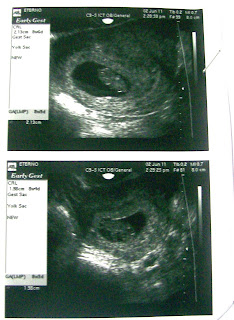

Hola chicas!!! Bueno les cuento que el Jueves 2/6 me hice la que tendría que haber sido mi segunda eco, pero en realiad fué la tercera porque el Viernes pasado tuve unas manchitas rosas y marrones y el doc me mandó a la guardia para que me hagan una eco y ver si estaba todo bien. Gracias a Dios estaba todo perfecto y el sangradito no era de los bebés. E jueves me hice la otra eco y ya miden 21mm cada uno, marcha todo muy bien!!!!

Ahora el 28/6 tengo la TN, tengo mucha ansiedad, espero que siga todo tan bien como hasta ahora. les dejo unas fotitos de los babys.